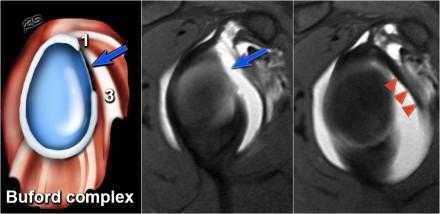

Комплекс Буфорда

Комплекс Буфорда это врожденный вариант строения суставной губы в виде отсутствия ее передневерхних отделов в области на 1-3 часа и утолщение средней плече-лопаточной связки.

Определяется в 1,5 % случаев.

На аксиальных изображениях слева может быть виден комплекс Буфорда.

Отсутствуют переднеие отделы суставной губы в области на 1-3 часв, утолщена средняя плече-лопаточная связка.

Утолщенная средняя плече-лопаточная связка не должна обшибочно приниматься за смещенную суставную губу.

Всегда по возможности необходимо прослеживать ход средней плече-лопаточная связки сверху вниз от фиброзно-хрящевой губы гленоида к плечевой кости.